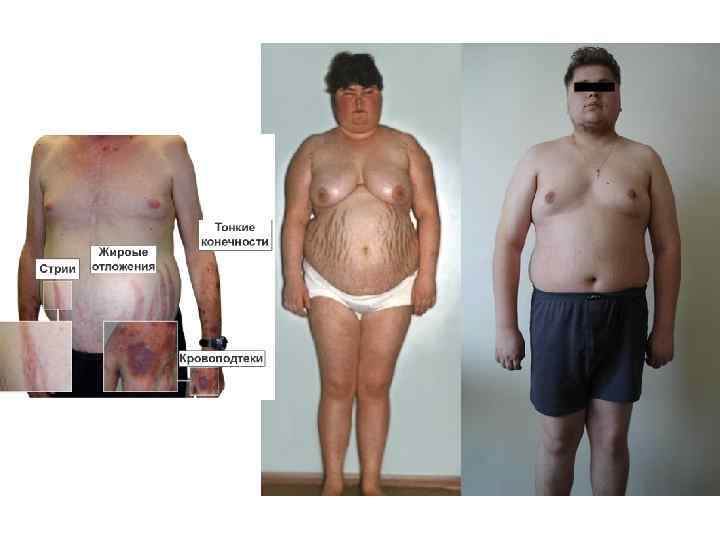

Синдром Иценко-Кушинга 1. Быстрое увеличение веса, ожирение туловища, луноподобное лицо с плеторой. 2. Стрии растяжения (шириной более 1 см, обычно белого цвета). 3. Подушечки жира над ключицами. 4. Нарушение толерантности к глюкозе. 5. Гипокалиемия. 6. Acne, особенно не на лице. 7. Гирсутизм. 8. Олигоменорея или аменорея до менопаузы. Специальные исследования 1. Высокий уровень кортизола в плазме крови (нормальные значения заболевания не исключают). 2. Повышенное содержание свободного кортизола в моче (наиболее важный специальный тест скрининга) в двух или трех последовательных 24 -часовых заборах мочи (при экскреции креатинина выше 10 мг/кг в день). 3. Увеличение выделения в суточном количестве мочи 11 -кетостероидов и 17 -оксикортикостероидов. При гиперкортицизме выделение 17 -ОКС превышает 16— 55 мкмоль/сутки. При опухолях надпочечников уровень АКТГ в плазме снижен (норма — 60— 120 пг/мл), при болезни Иценко—Кушинга он повышен, но до умеренных цифр, при АКТГ-продуцирующей опухоли — резко повышен. 4. Ночной тест подавления с дексаметазоном (наиболее важный специальный тест скрининга): отсутствие снижения содержания кортизола в плазме крови ниже 5 мкг/дл к 08: 00 после приема внутрь 1 мг дексаметазона в 23: 00 накануне. Информативна проба с дексаметазоном, когда больному назначается этот препарат по 2 мг каждые 6 ч в течение 48 ч, а после этого исследуется суточная экскреция 17 -ОКС. У больных болезнью Иценко—Кушинга суточная секреция 17 -ОКС снижается, при синдроме — не изменяется. 5. Определение АКТГ в плазме крови и другие тесты для более точной диагностики характера заболевания. 6. Для поиска первичной опухоли используют компьютерную томографию надпочечников и грудной клетки, ЯМР гипофиза, а также определяют содержание АКТГ в вене височной кости. • АКТТ может продуцировать рак легкого или опухоль средостения, опухоль яичников, поджелудочной железы и почек.

Синдром Иценко-Кушинга 1. Быстрое увеличение веса, ожирение туловища, луноподобное лицо с плеторой. 2. Стрии растяжения (шириной более 1 см, обычно белого цвета). 3. Подушечки жира над ключицами. 4. Нарушение толерантности к глюкозе. 5. Гипокалиемия. 6. Acne, особенно не на лице. 7. Гирсутизм. 8. Олигоменорея или аменорея до менопаузы. Специальные исследования 1. Высокий уровень кортизола в плазме крови (нормальные значения заболевания не исключают). 2. Повышенное содержание свободного кортизола в моче (наиболее важный специальный тест скрининга) в двух или трех последовательных 24 -часовых заборах мочи (при экскреции креатинина выше 10 мг/кг в день). 3. Увеличение выделения в суточном количестве мочи 11 -кетостероидов и 17 -оксикортикостероидов. При гиперкортицизме выделение 17 -ОКС превышает 16— 55 мкмоль/сутки. При опухолях надпочечников уровень АКТГ в плазме снижен (норма — 60— 120 пг/мл), при болезни Иценко—Кушинга он повышен, но до умеренных цифр, при АКТГ-продуцирующей опухоли — резко повышен. 4. Ночной тест подавления с дексаметазоном (наиболее важный специальный тест скрининга): отсутствие снижения содержания кортизола в плазме крови ниже 5 мкг/дл к 08: 00 после приема внутрь 1 мг дексаметазона в 23: 00 накануне. Информативна проба с дексаметазоном, когда больному назначается этот препарат по 2 мг каждые 6 ч в течение 48 ч, а после этого исследуется суточная экскреция 17 -ОКС. У больных болезнью Иценко—Кушинга суточная секреция 17 -ОКС снижается, при синдроме — не изменяется. 5. Определение АКТГ в плазме крови и другие тесты для более точной диагностики характера заболевания. 6. Для поиска первичной опухоли используют компьютерную томографию надпочечников и грудной клетки, ЯМР гипофиза, а также определяют содержание АКТГ в вене височной кости. • АКТТ может продуцировать рак легкого или опухоль средостения, опухоль яичников, поджелудочной железы и почек.